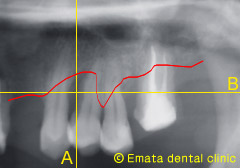

歯周病は歯槽骨(歯を支えている骨)が無くなる病気ですが、骨の無くなり方(骨欠損)の状態で、治療方法が決定します。従来は2次元的なレントゲンと歯周ポケット検査を頭の中で組み合わせて骨の欠損の形を想像していましたが、CTによる3次元的画像から、実際に骨の欠損状態がより確実にわかるようになりました。先日再生療法を行った治療例を紹介します。

従来のレントゲン画像です。骨がだいぶ喪失(赤線)して抜歯の適応でしょうか。 |